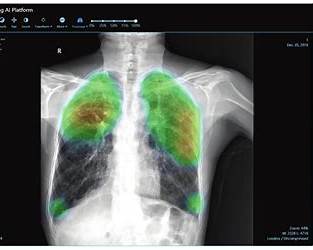

FtizisBioMed – “quả tim AI” trong phát hiện lao và ung thư phổi

Trong mạng lưới AI quốc gia, FtizisBioMed nổi lên như công cụ chủ lực trong phát hiện:

- Lao phổi.

- Ung thư phổi.

- Tổn thương tim – phổi.

- Và COVID-19.

Điểm đáng chú ý: AI này chỉ cần 0,8 giây để phân tích một phim X-quang và đưa ra gợi ý chẩn đoán.

Hàng triệu hình ảnh trên toàn Nga được xử lý mỗi năm, hỗ trợ trực tiếp vào quy trình khám chữa bệnh, đặc biệt ở các vùng xa – nơi thiếu bác sĩ chuyên khoa.